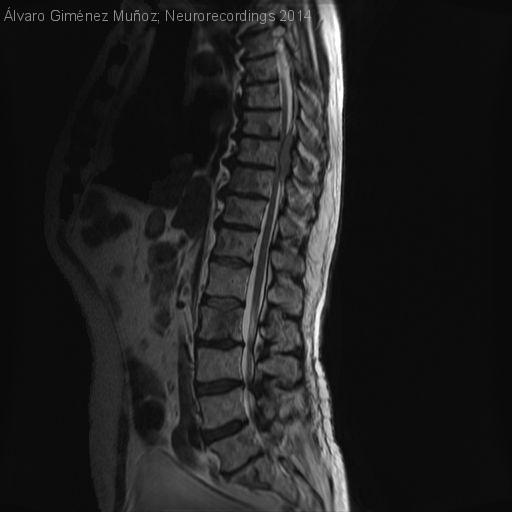

Paraparesia progresiva en paciente con mieloma múltiple

Hombre | 66 años

Diagnóstico final: Mielopatía compresiva por plasmocitoma epidural

Neurología: Patología de raquis

Etiología: Neoplasias

Paciente con antecedentes personales de mieloma múltiple con recaída ósea generalizada (lesiones líticas en varios arcos costales, iliovertebrales). Consulta por intenso dolor lumbar con pérdida de fuerza y sensibilidad en miembros inferiores de varias semanas de...